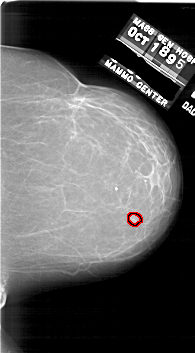

A_1748_1.LEFT_CC

LEFT_CC LINES 6601 PIXELS_PER_LINE 3691 BITS_PER_PIXEL 12 RESOLUTION 43.5 NON_OVERLAY

FILE: A_1748_1.RIGHT_CC.OVERLAY

TOTAL_ABNORMALITIES 1

ABNORMALITY 1

LESION_TYPE MASS SHAPE LOBULATED MARGINS CIRCUMSCRIBED

ASSESSMENT 3

SUBTLETY 3

PATHOLOGY BENIGN

TOTAL_OUTLINES 1

BOUNDARY